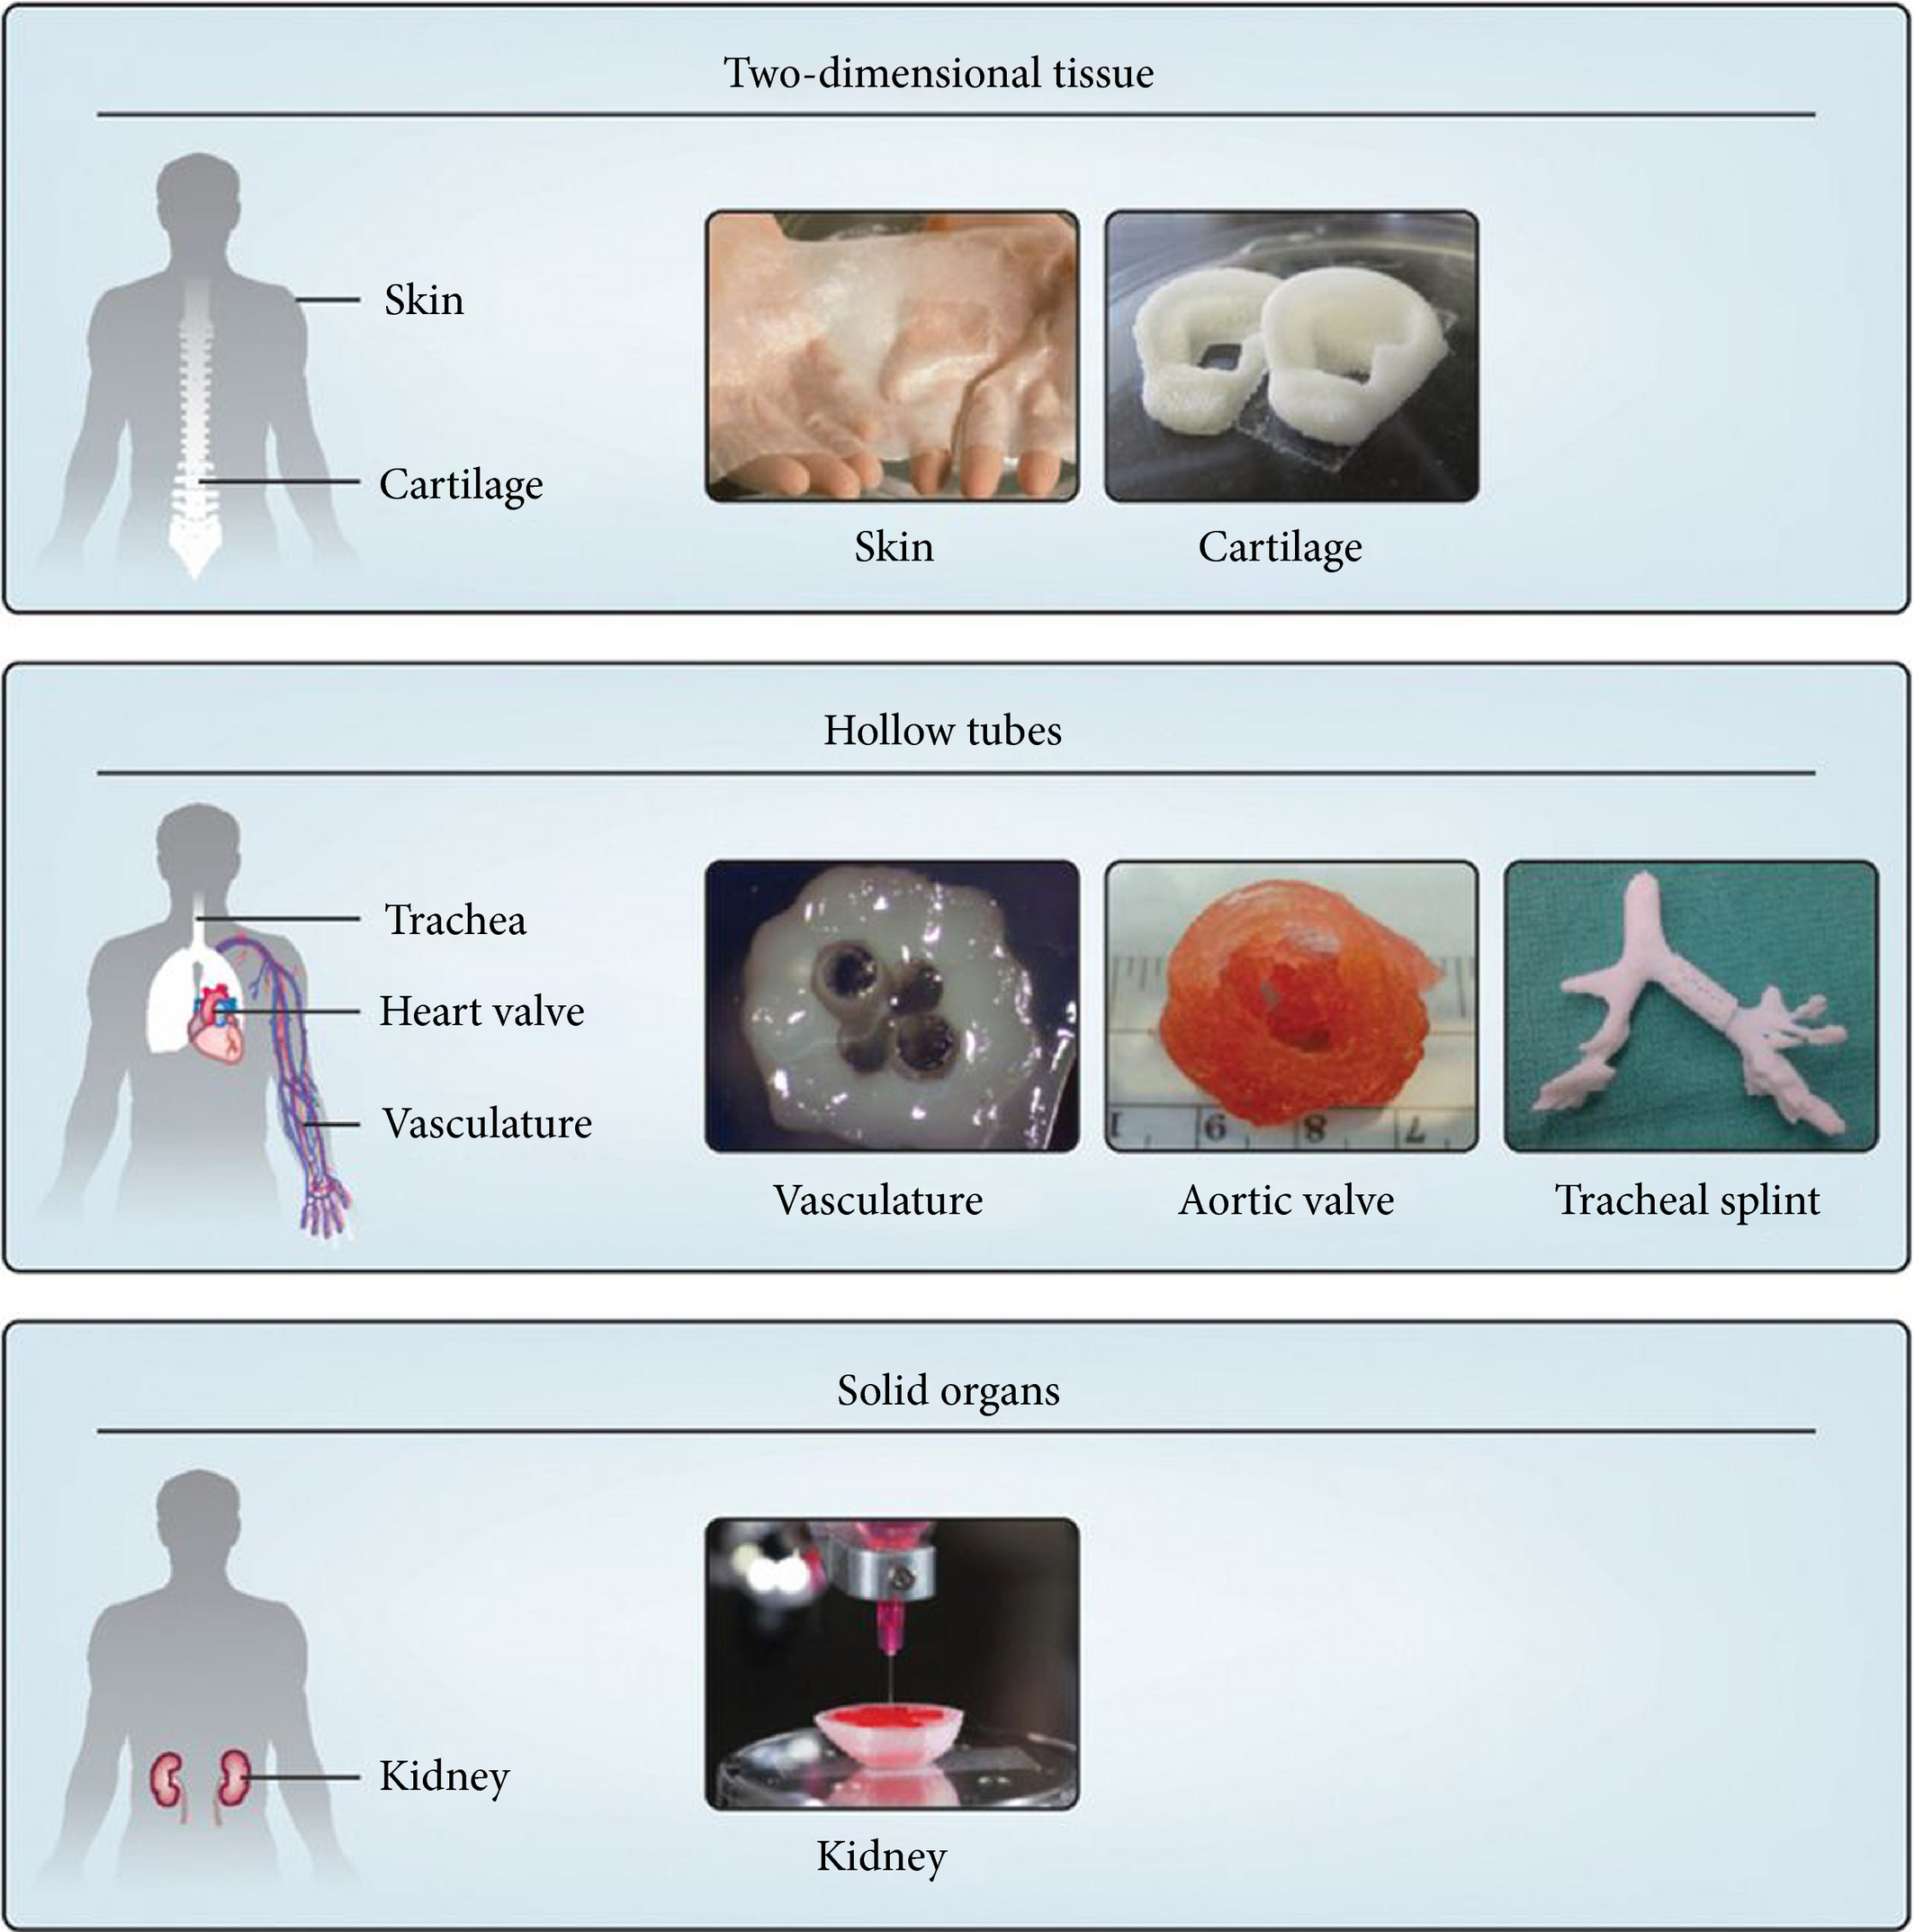

Perhaps the coolest of the applications (and unfortunately the least developed) is the 3D bioprinting of actual cell cultures for transplantation, although the successful fabrication of any surgery-ready major organs is yet to be realized. Making major strides in that direction, Kumar et al. managed to 3D print kidney micro-organoids – an economical source of kidney cells. With a number of developments to the technology and perhaps a change in environment (like the ISS), we could potentially see whole 3D printed replacement organs become an option in the coming decades.